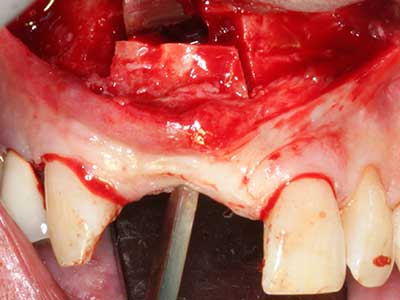

En la extracción de bloques óseos la piezocirugía también presenta ventajas adicionales: Además de la alta precisión en la osteotomía que ya se ha descrito antes, se ha comprobado que el uso de los delgados insertos de sierra resulta especialmente cuidadosas con el hueso. Frente a esto, sobre todo cuando se usan las fresas de Lindemann, cabe esperar pérdidas en la extracción significativamente más altas debido al mayor grosor de la parte frontal del cabezal (Lakshmiganthan, Gokulanathan et al. 2012). La separación basal que se necesita en particular en los injertos de bloque extraídos de forma retromolar se ve facilitada mediante sierras perpendiculares especialmente previstas a tal fin, lo que permite considerar que la cirugía piezoeléctrica es un procedimiento preciso y seguro para la obtención de bloques de hueso en el área retromolar (Happe 2007) (fig. 1-12).

Aplicación: Partición ósea / Cortical Split